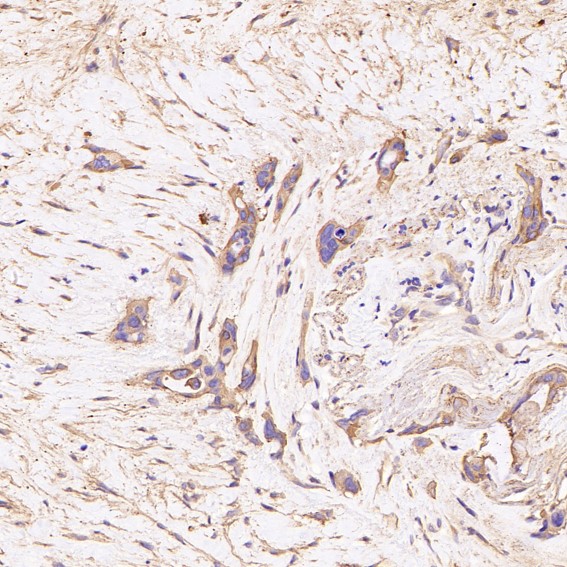

Immunohistochemical analysis of paraffin-embedded human colon carcinome, using GSK3 beta Antibody.

Immunohistochemical analysis of paraffin-embedded Human colon cancer, using the Antibody.

Immunohistochemical analysis of paraffin-embedded human colon carcinome, using GSK3 beta Antibody.

Immunohistochemical analysis of paraffin-embedded Human colon cancer, using the Antibody.